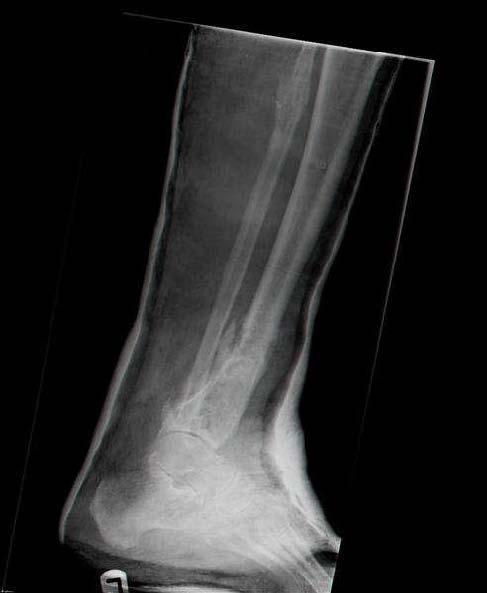

Мужчина, 33 года, резекция б\б кости по поводу остеомиелита после открытого перелома. Стандартная методика билокального остеосинтеза (рис 1 и 2). В конце удлинения выявилось неудовлетворительное взиморасположение перемещенного фрагмента и дистального отломка (рис 3). Планирование (рис 4).

Адаптация отломков гексаподом за 5 дней (рис 5). Замена гексапода на обычные штанги (рис 6 и 7)